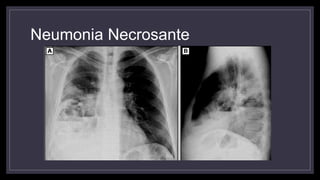

Neumonía Necrosante

• Se da en pacientes inmunodeprimidos y enfermos crónicos

• Asociada a Estafilococo Aureus (sobre todo meticilino resistentes y

positivos para Panton Valentine Leukocidin), Klebsiela, Anaerobios.

• Gran necrosis de tejido pulmonar

• Inicialmente se observan áreas radiolúcidas dentro de una

consolidación que luego confluyen para formar una cavidad que

contiene líquido.

Neumonia Necrosante